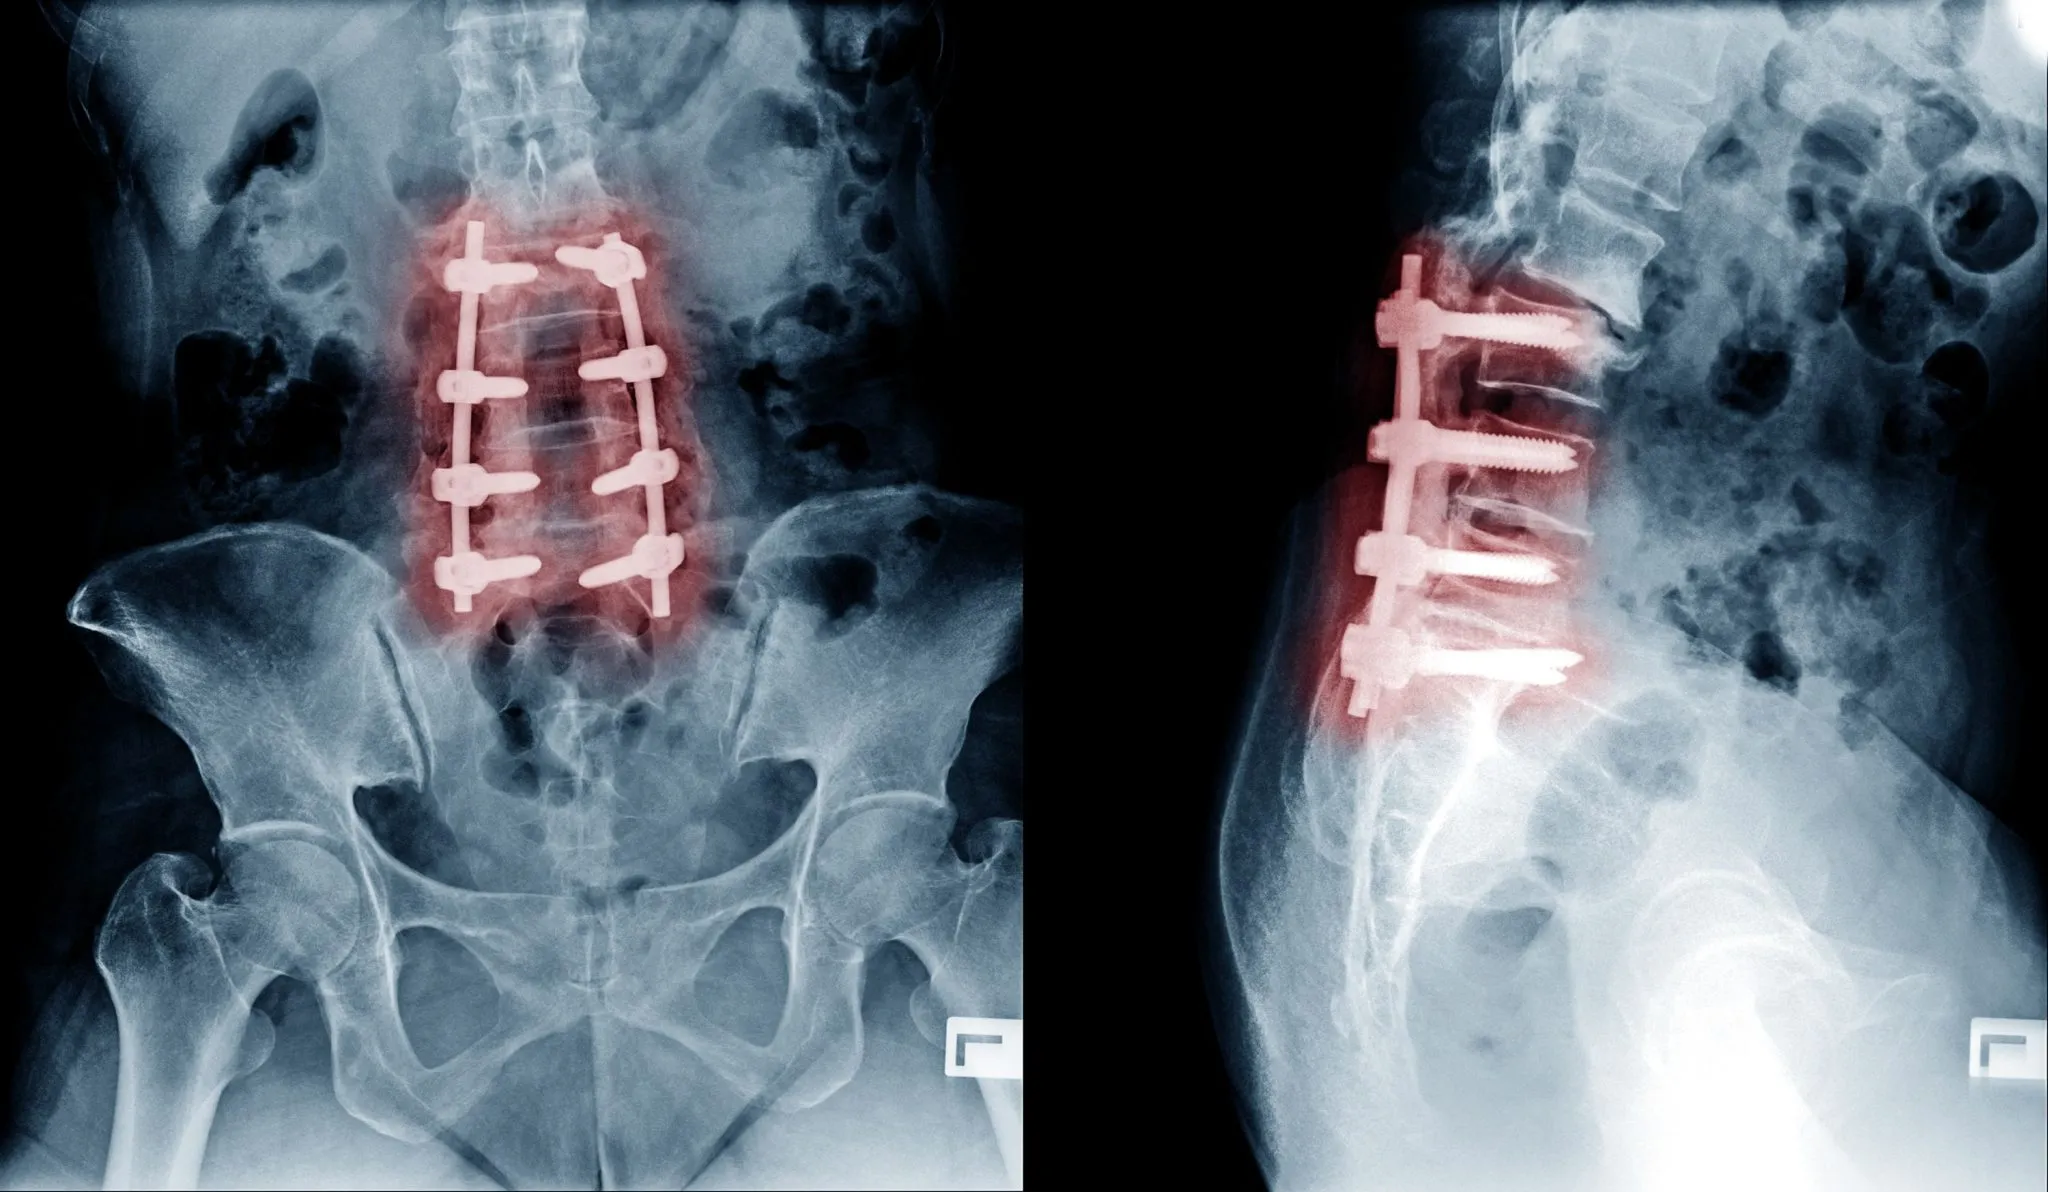

Why Spinal Fusion Is Usually Not the Answer

When a patient with a herniated disc or degenerative disc disease is referred to a traditional spine surgeon, one procedure dominates the conversation: spinal fusion. Fusion is presented as the definitive surgical solution, the way to finally end the suffering. The reality is considerably more complicated.

Spinal fusion works by permanently connecting two or more vertebrae using bone grafts, metal rods, screws, and cages. The goal is to eliminate motion at the painful segment and thereby reduce pain. But eliminating motion does not eliminate the disc inflammation or nerve compression that was generating the pain. It simply removes movement while leaving those underlying problems largely unaddressed.

The consequences of this approach are significant:

- Adjacent segment disease: when one level is fused, the vertebrae above and below must absorb the lost motion, accelerating their degeneration. Research shows that 20 to 30% of fusion patients develop adjacent segment disease requiring additional surgery within 10 years

- Revision surgery rates between 8% and 46% for all fusion patients

- Hospitalization of 3 to 5 days, followed by months of recovery

- Destruction of healthy surrounding muscles, ligaments, and bone during the procedure

- Permanent limitation of spinal flexibility

- High postoperative pain requiring opioid use

- Extensive scar tissue formation around the spine and nerves

Fusion also fails to address the most common cause of chronic discogenic back pain: the inflammatory, painful disc material itself. The source of the chemical pain signal is left in place. The nerve is still being irritated. And many patients find themselves in pain management indefinitely after surgery, never achieving the relief they were promised.

If you have been told that spinal fusion is your only option, we strongly encourage you to contact Deuk Spine Institute before proceeding. It is often not your only option. And it is very rarely the best one.